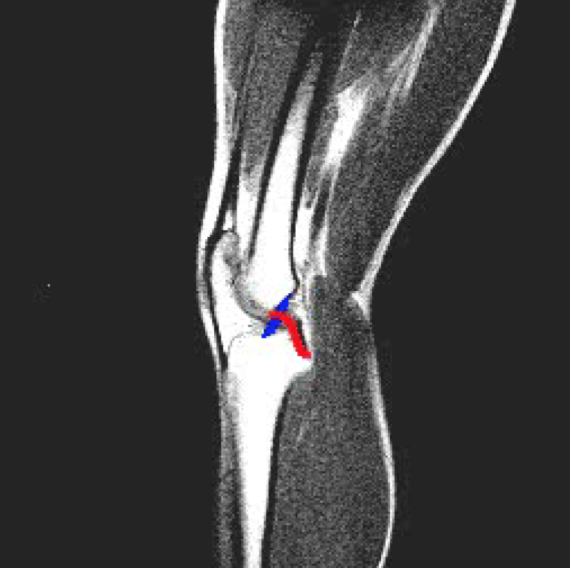

Anterior cruciate ligament origin and insertion:

APEX

Posterior cruciate ligament origin and insertion:

PAIN

Posterior collateral ligament (PCL) function:

Anterior collateral ligament (ACL) function: